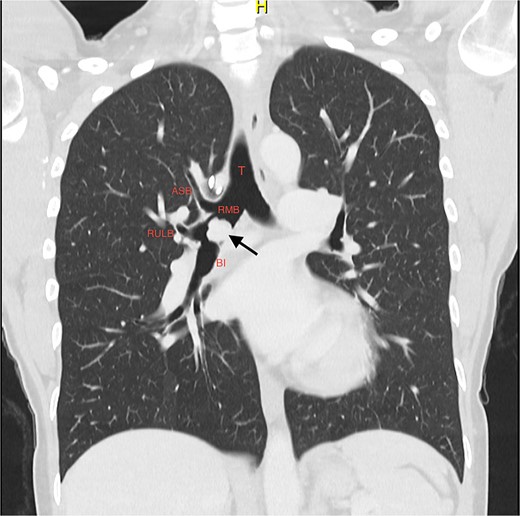

She initially underwent a rigid bronchoscopy, biopsy of the endobronchial tumour, cryoablation, and argon plasma for debulking. On direct visualization with the telescope the tumour was polypoid and was arising from the membranous portion of the right main bronchus (RMB) (Fig. 2).

Initial rigid bronchoscopy showing a polypoid mass originating from the membranous portion of the right main bronchus; BI, bronchus intermedius; RMB, right main bronchus.